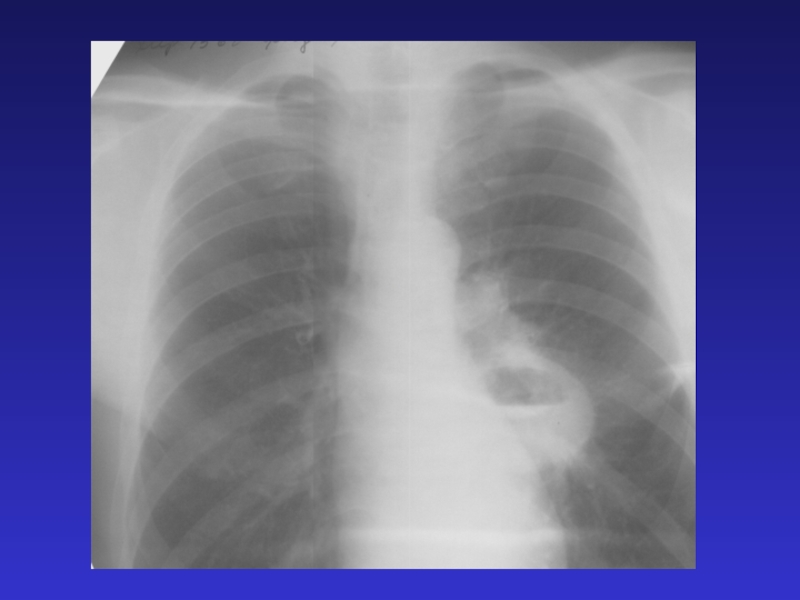

Слайд 29ДИССЕМИНАЦИЯ

ЧАСТЫЕ ПРИЧИНЫ:

диссеминированный туберкулез легких

метастазы

пневмония при сепсисе

РЕДКИЕ

ПРИЧИНЫ:

- пневмокониозы

- ацинозно-дольковый отек

- гемосидероз

- саркоидоз

- альвеолиты

ДИССЕМИНАЦИЯЧАСТЫЕ ПРИЧИНЫ: диссеминированный туберкулез легких метастазы пневмония при сепсисе РЕДКИЕ ПРИЧИНЫ:- пневмокониозы- ацинозно-дольковый отек - гемосидероз- саркоидоз-